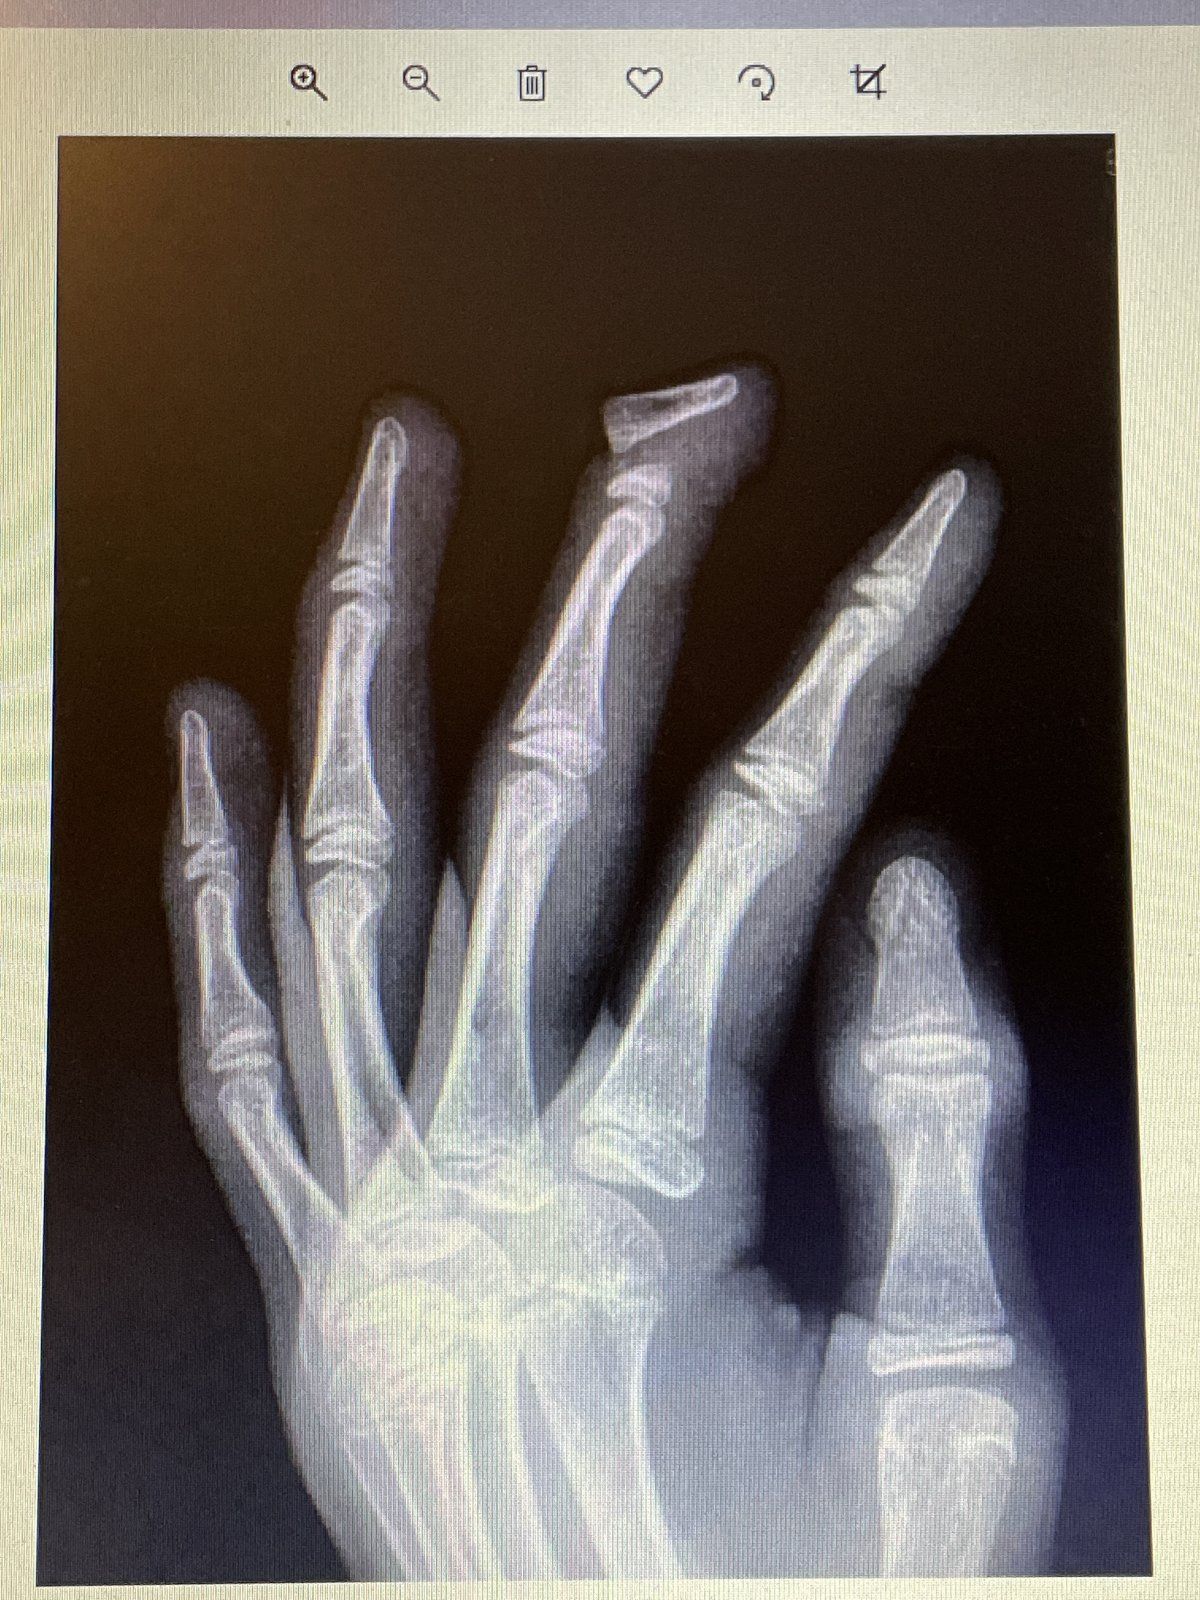

So for all of those in the US, I’m sure you have seen or played on a McDonalds play place. I was 12 years old I think and was as ambitious as ever. So you know how all the metal pipes are wrapped in that foam to prevent injury? And that the thin black net is attached to that? Well there was this low opening to this bigger play place, and I decided to be cool and swing under it. Well… the rope apparently caught my finger right above the joint, and completely snapped the bone. I didn’t even feel it until some kid told me I was bleeding, and then I looked down at my finger. I was rather calm, and remember running up to my mom and asking “is that the bone!??”. She then proceeded to freak out while all the other homeschool moms at the ‘meeting’ were also freaking out.

Here’s the xray

I’m very lucky I only broke one finger, because all my other fingers were severely bruised, which means they were very close to breaking. It was also the beginning of baseball season, so I had to sit out all season.